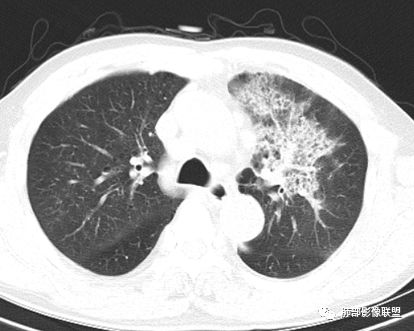

胸CT:左肺上叶前段实变,其周围及左肺上叶尖后段可见肺气肿背景下渗出性病变,病灶内可见支气管扩张,气道壁呈不规则增厚,双肺散在小结节状影;右肺下叶结节影,内可见空泡,边缘模糊,不规则。增强可见病灶内血管造影征,右肺门增大,纵隔淋巴结多发肿大。

晨读:左肺上叶大片实变影,周围可见磨玻璃影,小叶间隔增厚,部分支气管扩张,右肺下叶小结节,形态规则,边缘光滑,周围模糊晕征,中年男性,病史五天,白细胞正常,考虑NTM,奴卡,鉴别肺癌。

左肺上叶大片实变影,周围可见磨玻璃影,小叶间隔增厚,部分支气管扩张,右肺下叶结节,形态规则,边缘光滑,周围模糊晕征,中年男性。一元论:考虑炎性,建议治疗后复查除外腺癌。